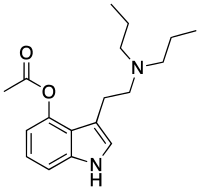

| 4-AcO-DPT | artificial | 4-OCOCH3 | CH2CH2CH3 | CH2CH2CH3 | 4-acetoxy-N,N-dipropyltryptamine | 1445751-75-6 |